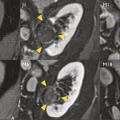

Pour chaque patient, un bilan d’hémostase est systématiquement réalisé avant la procédure. Pour les patients prenant des anticoagulants oraux, un relais par héparine de bas poids moléculaire est réalisé. Pour les antiagrégants plaquettaires, seul le clopidogrel doit être interrompu 5 jours avant. Le patient reçoit une prémédication par 1 g de paracétamol intraveineux 30 minutes avant la procédure. Il reste hospitalisé une nuit, mais une prise en charge ambulatoire est possible.La cryothérapie est réalisée sous anesthésie locale à l’aide d’un mélange de lidocaïne et de ropivacaïne. Contrairement à la radiofréquence ou aux micro-ondes où une seule électrode est insérée, la cryothérapie nécessite de mettre en place plusieurs aiguilles (cryoprobes) espacées au maximum de 15 mm afin de couvrir la totalité de la tumeur (fig. 1 ). Plus la tumeur est grosse, plus le nombre d’aiguilles à introduire est important. Il existe des abaques permettant de déterminer le nombre d’aiguilles optimal en fonction de la taille de la tumeur. Néanmoins, l’indication principale étant des tumeurs de stade T1a (< 4 cm de diamètre), le nombre moyen d’aiguilles est de 3, avec des extrêmes entre 2 et 5. Une injection de CO2 (carbodissection) ou de sérum physiologique (hydrodissection) est parfois nécessaire entre le rein et les organes adjacents afin de les éloigner de la zone d’ablation et les protéger.Les aiguilles sont mises en place sous tomodensitométrie et on vérifie leur bon positionnement. La dose délivrée lors d’une cryoablation rénale est inférieure aux niveaux de référence de dose recommandés pour une tomodensitométrie abdominale. Le traitement consiste en deux phases de cryoablation de 10 minutes entrecoupées d’une phase de réchauffement passif de 10 minutes également. L’effet cryogénique est obtenu par expansion d’un gaz (l’argon) dans une chambre de décompression de 2 à 4 cm de long située à l’extrémité de l’aiguille. Les températures minimales obtenues au contact de l’aiguille sont proches de -100 °C, en sachant qu’en moyenne la température de la tumeur se situe à -40 °C. La tomodensitométrie permet une excellente visualisation de la boule de glace, ce qui permet de monitorer l’ablation tout au long de la procédure. La boule de glace ainsi créée doit englober en totalité la tumeur et la dépasser de 5 mm afin d’avoir des marges de sécurité (fig. 2 ).6 En effet, le bord de la boule de glace est à l’isotherme 0 °C, qui n’est pas létal pour les tissus.Après traitement, le suivi des patients s’effectue par tomodensitométrie ou par imagerie par résonance magnétique (IRM), typiquement à 1 mois, 3 mois, 6 mois et 1 an, puis tous les ans. La zone d’ablation se rétracte progressivement et se fibrose, sans tumeur résiduelle visible (fig. 3 ). Pour les tumeurs de moins de 2 cm, le zone d’ablation disparaît parfois en totalité, laissant juste une encoche à la surface du rein (fig. 4 ). Les effets secondaires sont rares, la cryoablation étant mieux tolérée que les techniques d’ablation fondées sur le chauffage des lésions, en particulier pour les lésions proches de la voie excrétrice.7